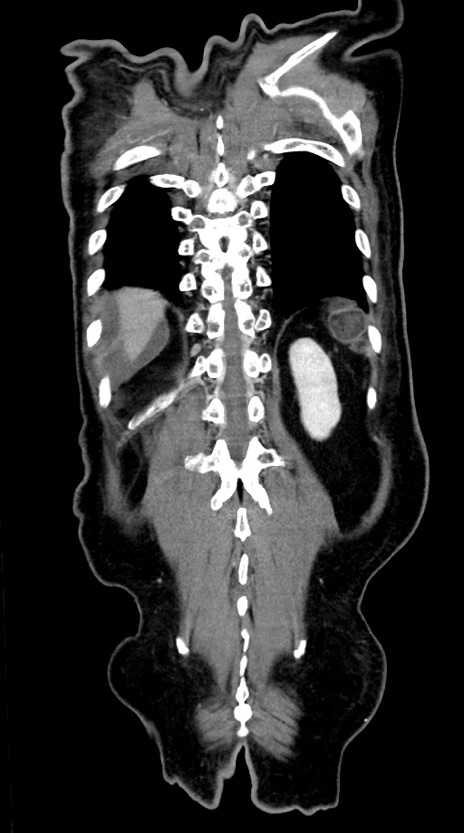

症例28(冠状断像)

【症例】60歳代男性

【主訴】嘔吐

【現病歴】胃癌にて胃全摘後。食思不振が悪化し、夜中に嘔吐することがある。

【既往歴】胃癌、胃全摘、脾摘、胆摘後

【データ】WBC 5900、CRP 10.56